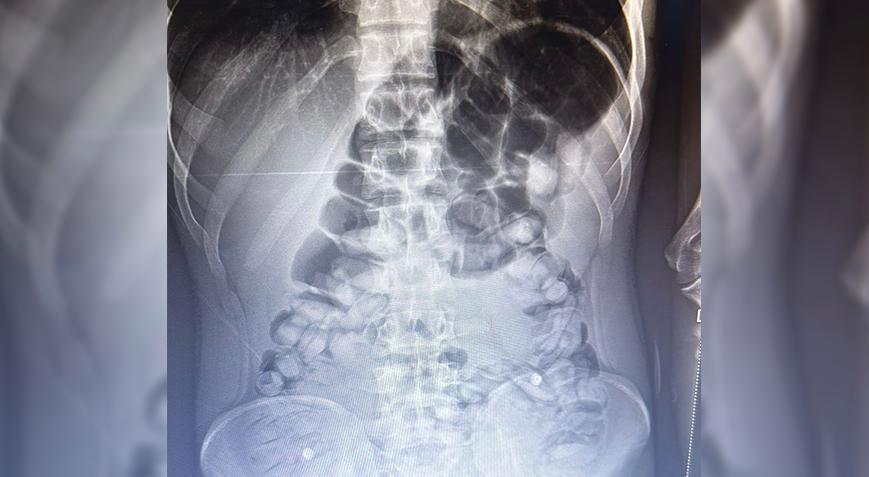

Erzurum’da, yolcu otobüsünde şüphe üzerine hastanede röntgeni çekilen yolcunun midesinde Afyon sakızı, tespit edildi.

Burada rdöntgeni çekilen yolcunun midesinde uyuşturucu tespit edildi. İlaç verilen yolcu, 1 kilo 134 gram Afyon sakızını doğal yollarla çıkardı.